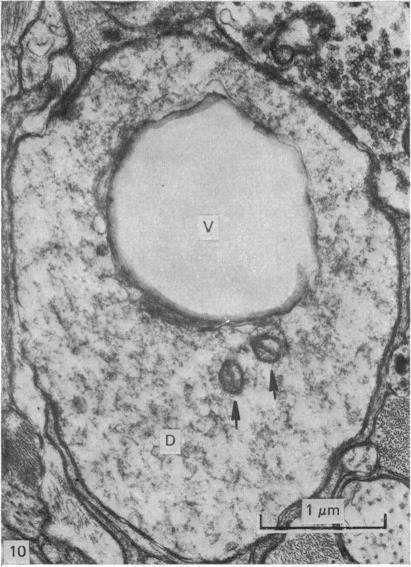

An electron microscopical study of the intermediolateral nucleus of the monkey has shown that the neurons could be classified into at least three main types. The perikarya and proximal dendrite of Types I and II neurons were almost completely covered with astrocytic processes. Both these types of neurons were characterized by prominent profiles of rough endoplasmic reticulum arranged in parallel stacks in Type I and in small aggregates in Type II. The Golgi apparatus was well developed in both types. In contrast, Type III neurons, which were consistently smaller than the other two types, were only partially covered by astrocytic processes, their meagre RER consisted of single short strands of ribosome-studded cisterns randomly dispersed in the cytoplasm and their Golgi apparatus was poorly dveloped. The nuclear outline of all three types of neuron was irregular, but that of Type III neurons was deeply indented. Axosomatic synapses were rarely observed in Types I and II neurons but were common in Type III neurons. Axon terminals in the intermediolateral nucleus could also be divided into three main classes according to their synpatic vesicular morphology. R-boutons contained round agranular vesicles, DCV-boutons contained a mixture of agranular and large dense-cored vesicles and F-boutons contained flattened or ellipsoidal vesicles. All three classes of axon terminals formed simple axodendritic synapses and also took part in the formation of glia-encapsulated glomerular synapses in which the most common arrangement was that of a central dendrite which was synaptically contacted by axon terminals. F-boutons formed axosomatic synapses with all three types of neurons, R-boutons synapsed commonly on Type III neurons and only occasionally on Type II neurons, while DCV-boutons were rarely seen to form axosomatic synapses. No axo-axonal synapses were observed.

对猴子中间外侧核的电子显微镜研究表明,神经元可至少分为三种主要类型。I型和II型神经元的胞体和近端树突几乎完全被星形胶质细胞的突起所覆盖。这两种类型的神经元的特征是,I型神经元中粗糙内质网呈平行堆叠的显著轮廓,II型神经元中则呈小聚集体。两种类型的神经元中高尔基复合体均发育良好。相比之下,III型神经元始终比其他两种类型小,仅部分被星形胶质细胞的突起覆盖,其稀少的粗面内质网由随机分散在细胞质中的单条短核糖体附着的池状结构组成,其高尔基复合体发育不良。所有三种类型神经元的核轮廓均不规则,但III型神经元的核轮廓有深深的凹陷。I型和II型神经元中很少观察到轴体突触,但III型神经元中很常见。根据其突触小泡形态,中间外侧核中的轴突终末也可分为三大类。R型终扣含有圆形无颗粒小泡,DCV型终扣含有无颗粒和大的致密核心小泡的混合物以及F型终扣含有扁平或椭圆形小泡。所有三类轴突终末均形成简单的轴树突触,也参与形成胶质细胞包裹的小球状突触,其中最常见的排列方式是中央树突与轴突终末形成突触联系。F型终扣与所有三种类型的神经元形成轴体突触,R型终扣通常与III型神经元形成突触,仅偶尔与II型神经元形成突触,而DCV型终扣很少形成轴体突触。未观察到轴-轴突触。